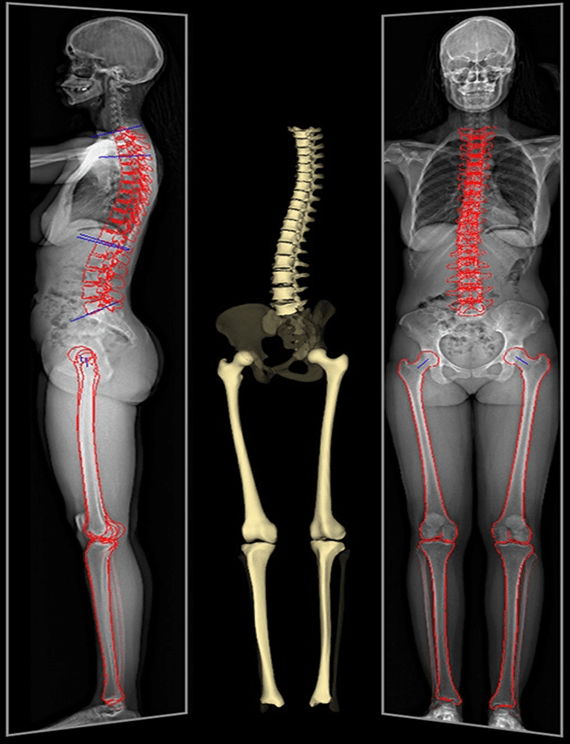

Πρόκειται για προηγμένες ψηφιακές ακτινογραφίες που απεικονίζουν σε μία ενιαία, υψηλής ευκρίνειας εικόνα ολόκληρη τη σπονδυλική στήλη (Full Spine) ή τα κάτω άκρα (Full Leg). Σε αντίθεση με τις απλές ακτινογραφίες που εστιάζουν σε ένα μόνο σημείο, η μέθοδος αυτή επιτρέπει στον γιατρό να αξιολογήσει τη συνολική ισορροπία του σώματος, εξετάζοντας πώς η στάση της σπονδυλικής στήλης επηρεάζει τη λεκάνη και τα πόδια.

Η εξέταση πραγματοποιείται ενώ ο ασθενής στέκεται όρθιος (υπό φόρτιση). Με αυτόν τον τρόπο, αποτυπώνεται η πραγματική κατάσταση του σκελετού υπό την επίδραση της βαρύτητας, αποκαλύπτοντας αποκλίσεις που θα ήταν αδύνατο να εντοπιστούν σε κατάκλιση (ξαπλωμένος).

- Ανισοσκελία: Όταν το ένα πόδι είναι έστω και λίγα χιλιοστά κοντύτερο από το άλλο, προκαλείται ασυμμετρία στη λεκάνη και πόνος στη μέση. Η ψηφιακή μέτρηση Full Leg προσφέρει ακρίβεια χιλιοστού.

- Ορθοπεδικά Χειρουργεία: Απαραίτητη για τον προεγχειρητικό σχεδιασμό (π.χ. ολική αρθροπλαστική ισχίου ή γόνατος) ώστε να επιτευχθεί η τέλεια ευθυγράμμιση.